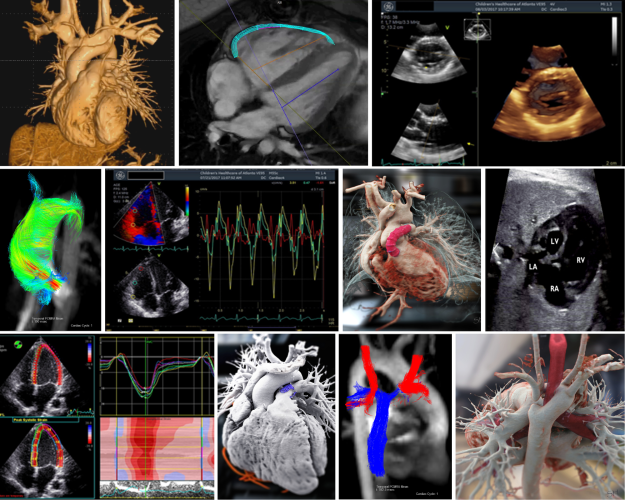

The CIRC has dedicated space, equipment and experienced staff to provide high quality cardiovascular imaging services as well as post-processing of previously acquired images using specialized software. These services include performance of a routine complete or limited congenital or non-congenital two-dimensional echocardiography, color and spectral Doppler imaging; advanced echocardiographic imaging including three-dimensional echocardiography, tissue Doppler imaging, strain and strain rate imaging; stress echocardiography and cardiac magnetic resonance imaging. CIRC has also launched a program for assessment of vascular health in pediatric patients that includes non-invasive assessment of endothelial function using brachial artery flow-mediated dilation, measurement of arterial stiffness using applanation tonometry and assessment of structural arterial changes using carotid imaging. In 2015, CIRC expanded our research administration offerings to include data coordinating center and core imaging site capabilities for multi-center studies.

Cardiovascular Imaging Research Core (CIRC) provides non-invasive cardiovascular imaging support for investigators involved in clinical research involving infants, children and adolescents. The CIRC has dedicated space, equipment and experienced staff to provide high quality cardiovascular imaging services as well as post-processing of previously acquired images using specialized software. These services include performance of a routine complete or limited congenital or non-congenital two-dimensional echocardiography, color and spectral Doppler imaging, advanced echocardiographic imaging including three-dimensional echocardiography, tissue Doppler imaging, strain and strain rate imaging, stress echocardiography and cardiac magnetic resonance imaging. CIRC has also launched a program for assessment of vascular health in pediatric patients that includes non-invasive assessment of endothelial function using brachial artery flow-mediated dilation, measurement of arterial stiffness using applanation tonometry and assessment of structural arterial changes using carotid imaging.

CIRC offers a number of services:

- Echocardiograms

- Complete and limited non-congenital

- Complete and limited congenital

- Color and spectral Doppler

- 3-D imaging

- Strain and strain rate imaging

- Tissue Doppler imaging

- Cardiac MRI (logistical and analysis support)